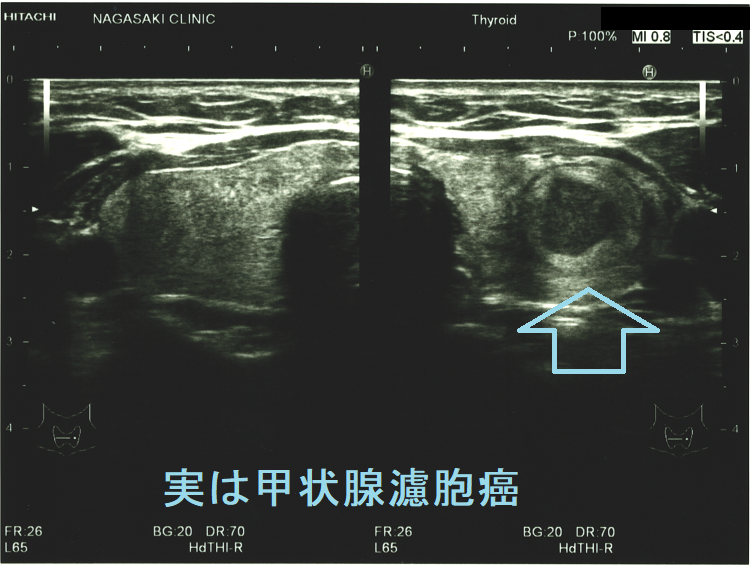

超音波(エコー)上、甲状腺濾胞癌は良性濾胞腺腫と類似しますが、

- 内部が低エコー・不均質、いわゆる「Tumor in Tumor(tubercle-in-nodule signs)」(腫瘍の中に腫瘍がある)のパターンを取ることがある 石灰化が顕著(微細、粗大、辺縁石灰化)

- 境界性状が良性濾胞腺腫よりも粗雑。

- ハロー(周辺部低エコー)を全周性に認めれば、良性濾胞腺腫の可能性高いが、不規則なハロー(境界部低エコー帯)の一部途絶、 肥厚等があれば甲状腺濾胞癌を強く疑う

- 内部血流が非常に多い

一目見て甲状腺癌ですが、濾胞性腫瘍や濾胞癌には見えない甲状腺腫瘍もあります。かといって甲状腺乳頭癌でもなく、あえて言うなら他臓器原発の転移性甲状腺癌が最も疑われる見え方です。

ケース1(微小浸潤型濾胞癌)

穿刺細胞診しても濾胞細胞のみ、術中の迅速病理標本でも濾胞性腫瘍、摘出標本で初めて被膜浸潤が見つかり、微小浸潤型濾胞癌の確定診断が付きました。